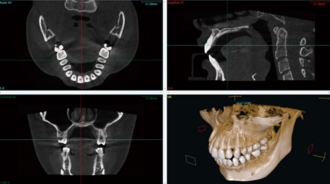

CTスキャン検査

インプラント(人工歯根)治療を適切に行うためには、顎の骨の状態を詳しく調べることが重要です。

そこで、CTスキャン検査を行うことによって顎の骨の断面画像を撮影し、その画像を見ながら治療の計画を立てます。より安全で、無理の無い治療を受けることが出来る最新の方法です。

当院でCTを撮り、コンピュータを使って画像診断をし、精度の高い検査を実施しております。

この検査の結果に基づいて、最適なインプラント治療の計画を立て、十分に納得していただけるようご説明いたします。